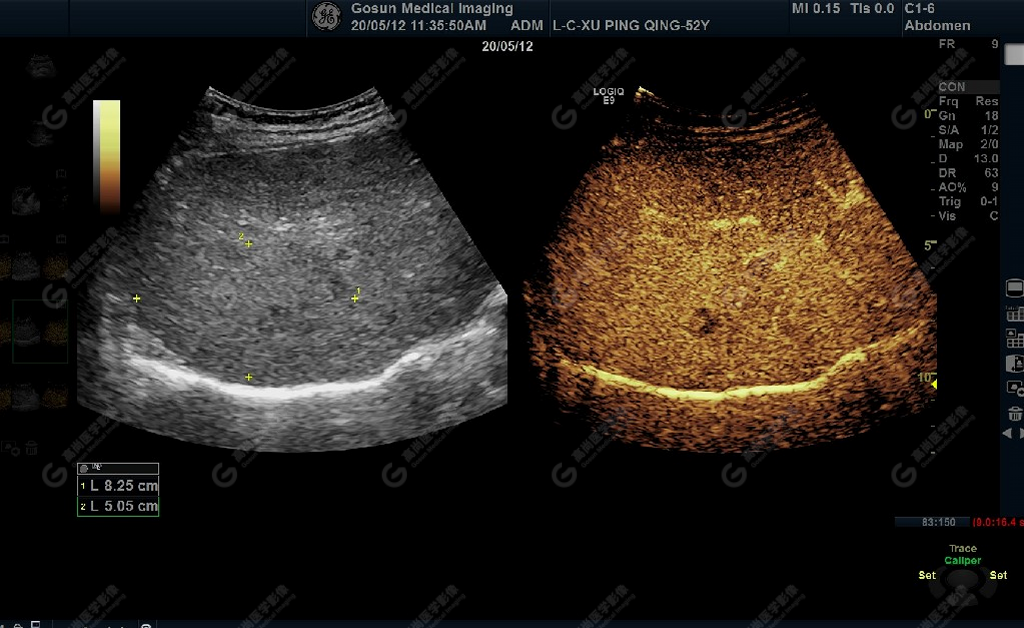

延遲期肝S7局部回聲減低,范圍約82mm×50mm

超聲所見肝包膜不光滑,實質(zhì)回聲增粗,不均勻,以右葉顯著,肝內(nèi)可見散在高回聲結(jié)節(jié),最大約7mm×5mm,邊界清,形態(tài)規(guī)則,CDFI顯示高回聲結(jié)節(jié)未見明顯異常血流信號。門靜脈主干內(nèi)徑約14mm,門靜脈右支管腔內(nèi)見實性低回聲,大小約23mm×14mm,邊界不清,形態(tài)不規(guī)則,局部與肝組織分界不清,CDFI:門靜脈主干血流緩慢,左支血流充盈好,右支血流充盈缺損,低回聲內(nèi)未見明顯血流信號。超聲造影:經(jīng)左側(cè)肘靜脈團(tuán)注超聲造影劑sonovue2.0ml。肝組織開始增強(qiáng)時間8秒,病灶開始增強(qiáng)時間11秒,邊界清晰。脈期呈均勻高增強(qiáng),至門脈期和延遲期消退為低增強(qiáng)。延遲期肝S7段局部回聲減低,范圍約82mm×50mm,內(nèi)見一低增強(qiáng)區(qū),范圍約13mm×16mm。

超聲提示門靜脈內(nèi)實性占位病變(考慮癌栓可能)

肝S7段異常回聲(不排除原發(fā)性肝Ca,建議進(jìn)一步檢查)